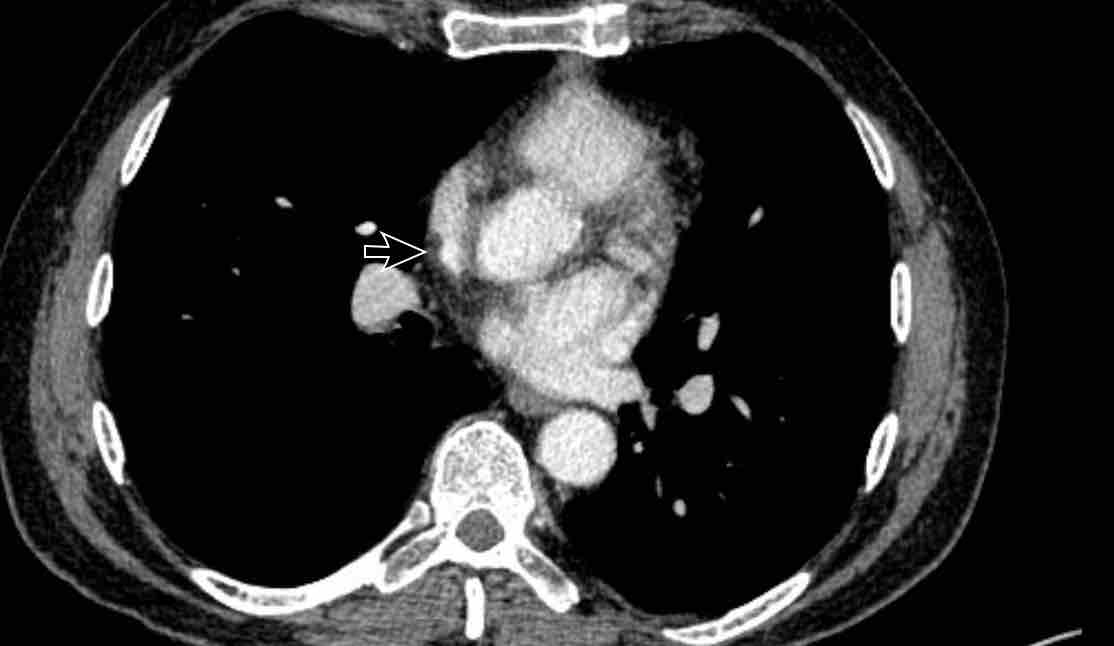

Hình ảnh

Bệnh nhân này được lên kế hoạch cắt thùy trên phải do ung thư phổi và bất thường mạch máu này ban đầu đã bị bỏ sót trên hình ảnh CT.

Những hệ quả trong phẫu thuật của bất thường như vậy nhấn mạnh tầm quan trọng của việc không bỏ sót các biến thể này.

Cuộn qua các hình ảnh.

PAPVR bên trái phát hiện tình cờ với dẫn lưu trên tim của máu từ thùy trên trái vào tĩnh mạch tay đầu trái (các mũi tên).